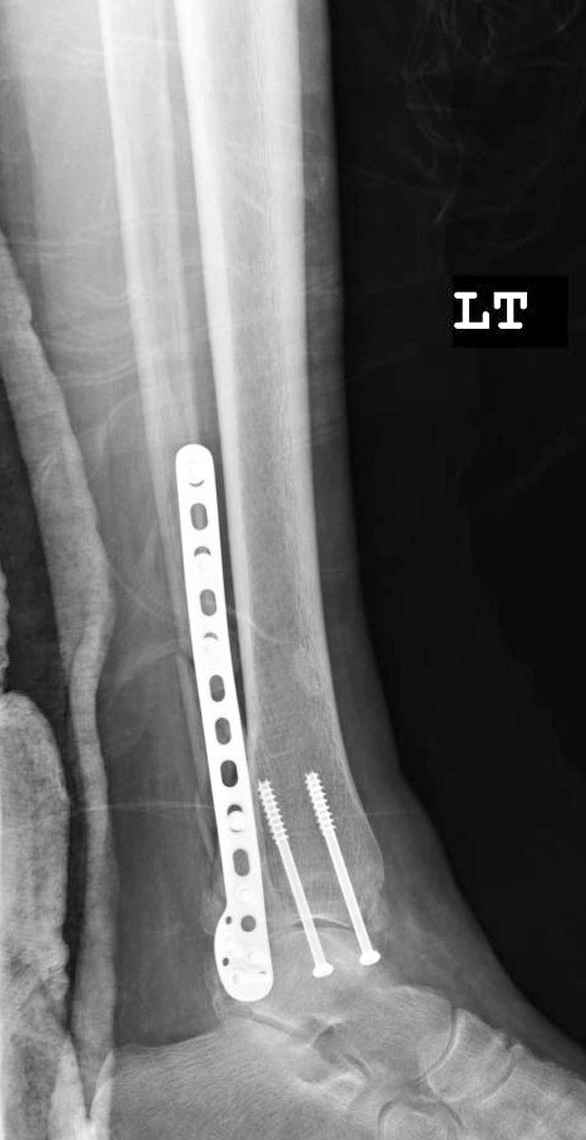

На 4-й неделе убрал спицы, с 7-й недели начал ЛФК, дозированную нагрузку, физиопроцедуры, массаж. Назначил хондропротекторы. Получилось вот что.

Rg-05.JPG

Удалены спицы, а гипса не было? 3-х лодыжечный перелом фиксировать 4 недели недостаточно. Что и подтверждается на последнем снимке - есть тенденция к подвывиху кнаружи, кзади... Что будет дальше, когда пациент начнет давать полную нагрузку?

Малоберцовая выглядит коротковатой. Профиль как-то мутный. Вообще, неплохо было бы сделать снимки в сравнении со здоровой.

Конечно, малоберцовая укорочена, надо сделать косой - мортиз снимок, тогда будеть понятно, на сколько.